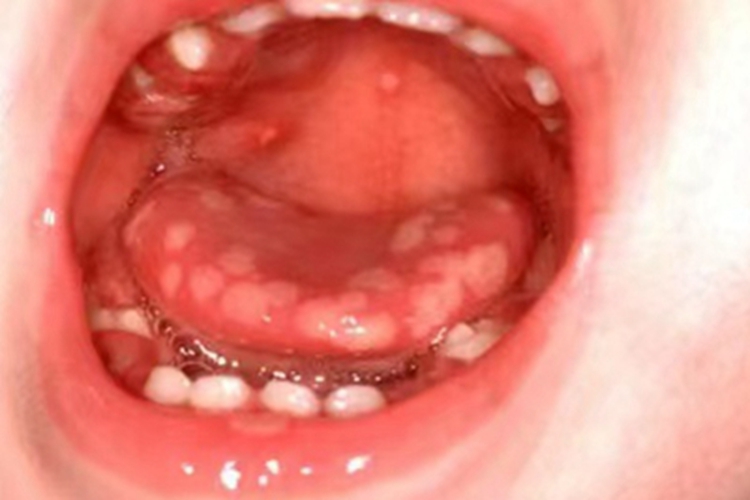

原发性口腔单纯性疱疹可见舌头发病时有水疱形成,壁薄透明,可形成溃疡,相互融合。单纯疱疹感染致病,可用药治疗。

原发性口腔单纯性疱疹发病前常出现发热、头痛、疲乏不适、全身肌肉疼痛、咽喉肿痛等急性症状,下颌下和颈上淋巴结肿大触痛。可见舌头发病时,有针头大小、壁薄透明的水疱,留有表浅溃疡,可相互融合成较大的溃疡,覆盖白色假膜。